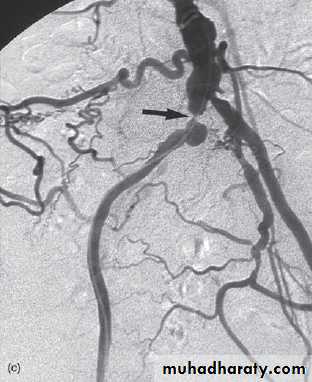

Digital subtraction angiography

Digital subtraction is a process whereby a computer removes unwanted information from a radiographic image. Digital subtraction is particularly useful for angiography, referred to as DSA.

Mask image contrast image subtracted image